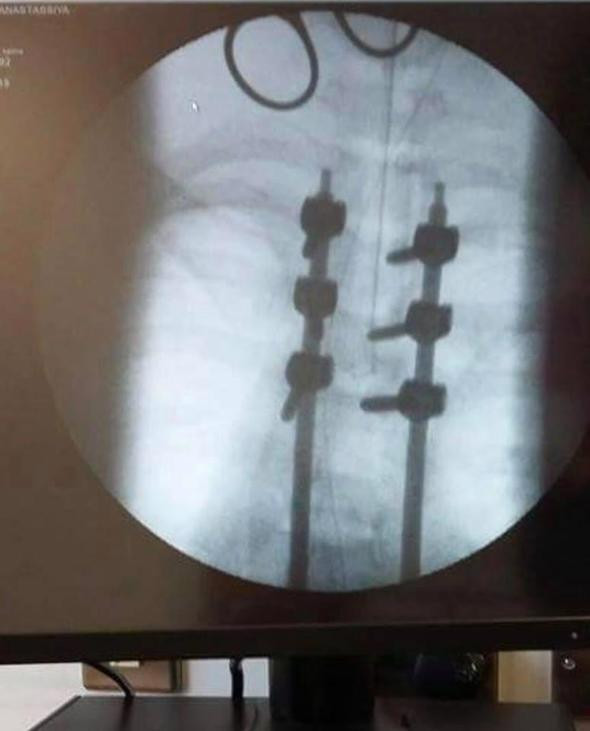

Sabah dönüş yolunda Anastassiya ve Beres kaza yaptı. Anastassiya’nın yaraları çok kötüydü, hemen Royal Victoria Hastanesi’ne kaldırıldı. Paul, Anastassiya eve gelmeyince endişelendi, telefonunu aramak için eline aldığında hastaneden gelen 11 cevapsız arama gördü. Hastane, kızın yaşayamayacağını hemen gelmeleri gerektiğini söyledi.Anastassiya’nın beyninde kanama vardı, 12 kaburgası kırılmıştı ve kırıklar ciğerlerine batıyordu; boynunda, omurgasında, omuzlarında kırıklar vardı. Komaya girmişti. 6 hafta sonra komadan çıktığında bir daha asla yürüyemeyeceğini öğrendi. Belinden aşağısı, omurgası ne kadar düzeltilmiş olsa da, sakat kalmıştı.